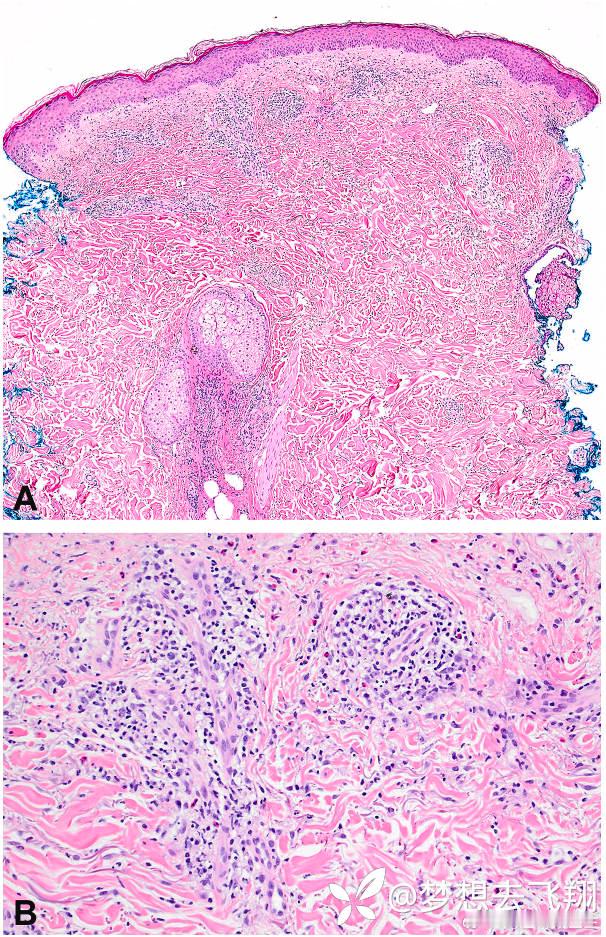

皮肤活检显示轻微海绵状,伴有浅层至深部真皮血管周围、附件周围和间质淋巴组织细胞浸润,伴有中性粒细胞和嗜酸性粒细胞的混合(见图2)。

对病灶进行了两次穿刺活检,显示轻度海绵状,伴有浅表至中皮血管周围、附件周围和间质淋巴组织细胞浸润,伴有频繁的嗜酸性粒细胞和中性粒细胞,最符合具有间质性肉芽肿环状背景的超敏反应(见图3)。